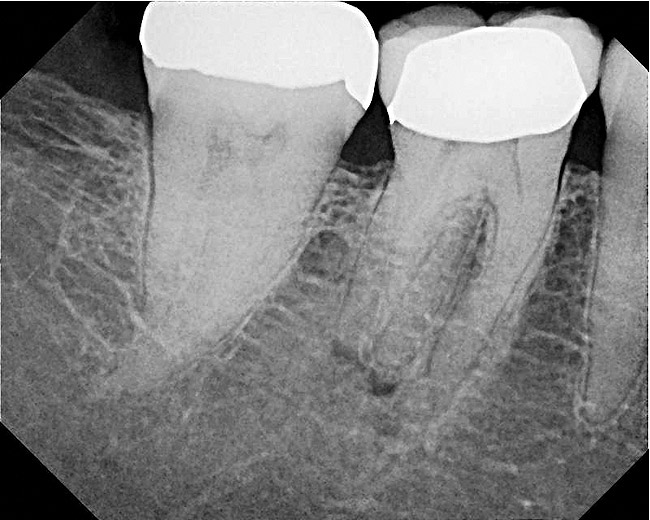

A 42-year-old woman presents for emergency treatment with a chief complaint of severe pain over the past 2 days in her upper jaw. The patient attributes the pain to tooth No. 3, as it received endodontic therapy 2 years ago (Figure 1). She complains of severe (pain score of 9/10), dull, throbbing pain in the right side of the face, jaws, and cheek that radiates into the temple with episodes of acute sharp pain, which is more severe at night, and appears to be stemming from the maxillary right molar (tooth No. 3). The patient has been awakened with pain over the past couple of nights and takes 600 mg of ibuprofen for relief. The patient also complains of a history of cold sensitivity from that tooth over the past couple of months and a history of low-grade chewing pain ever since the root canal. The past dental history is significant for a recent prophylaxis and fluoride treatment within the past month, and two fillings in the maxillary left side (teeth Nos. 12 and 14), and a crown in tooth No. 30 within the past 3 months (Figure 2). The patient’s medical history is insignificant, with no allergies reported. Extraoral tests are insignificant for objective findings. Intraoral tests show that tooth No. 3 is sensitive to percussion (3/10) and the radiograph shows a localized periapical radiolucency associated with the mesiobuccal (MB) root of this tooth.

Figure 1  Preoperative view of tooth No. 3.

Figure 1